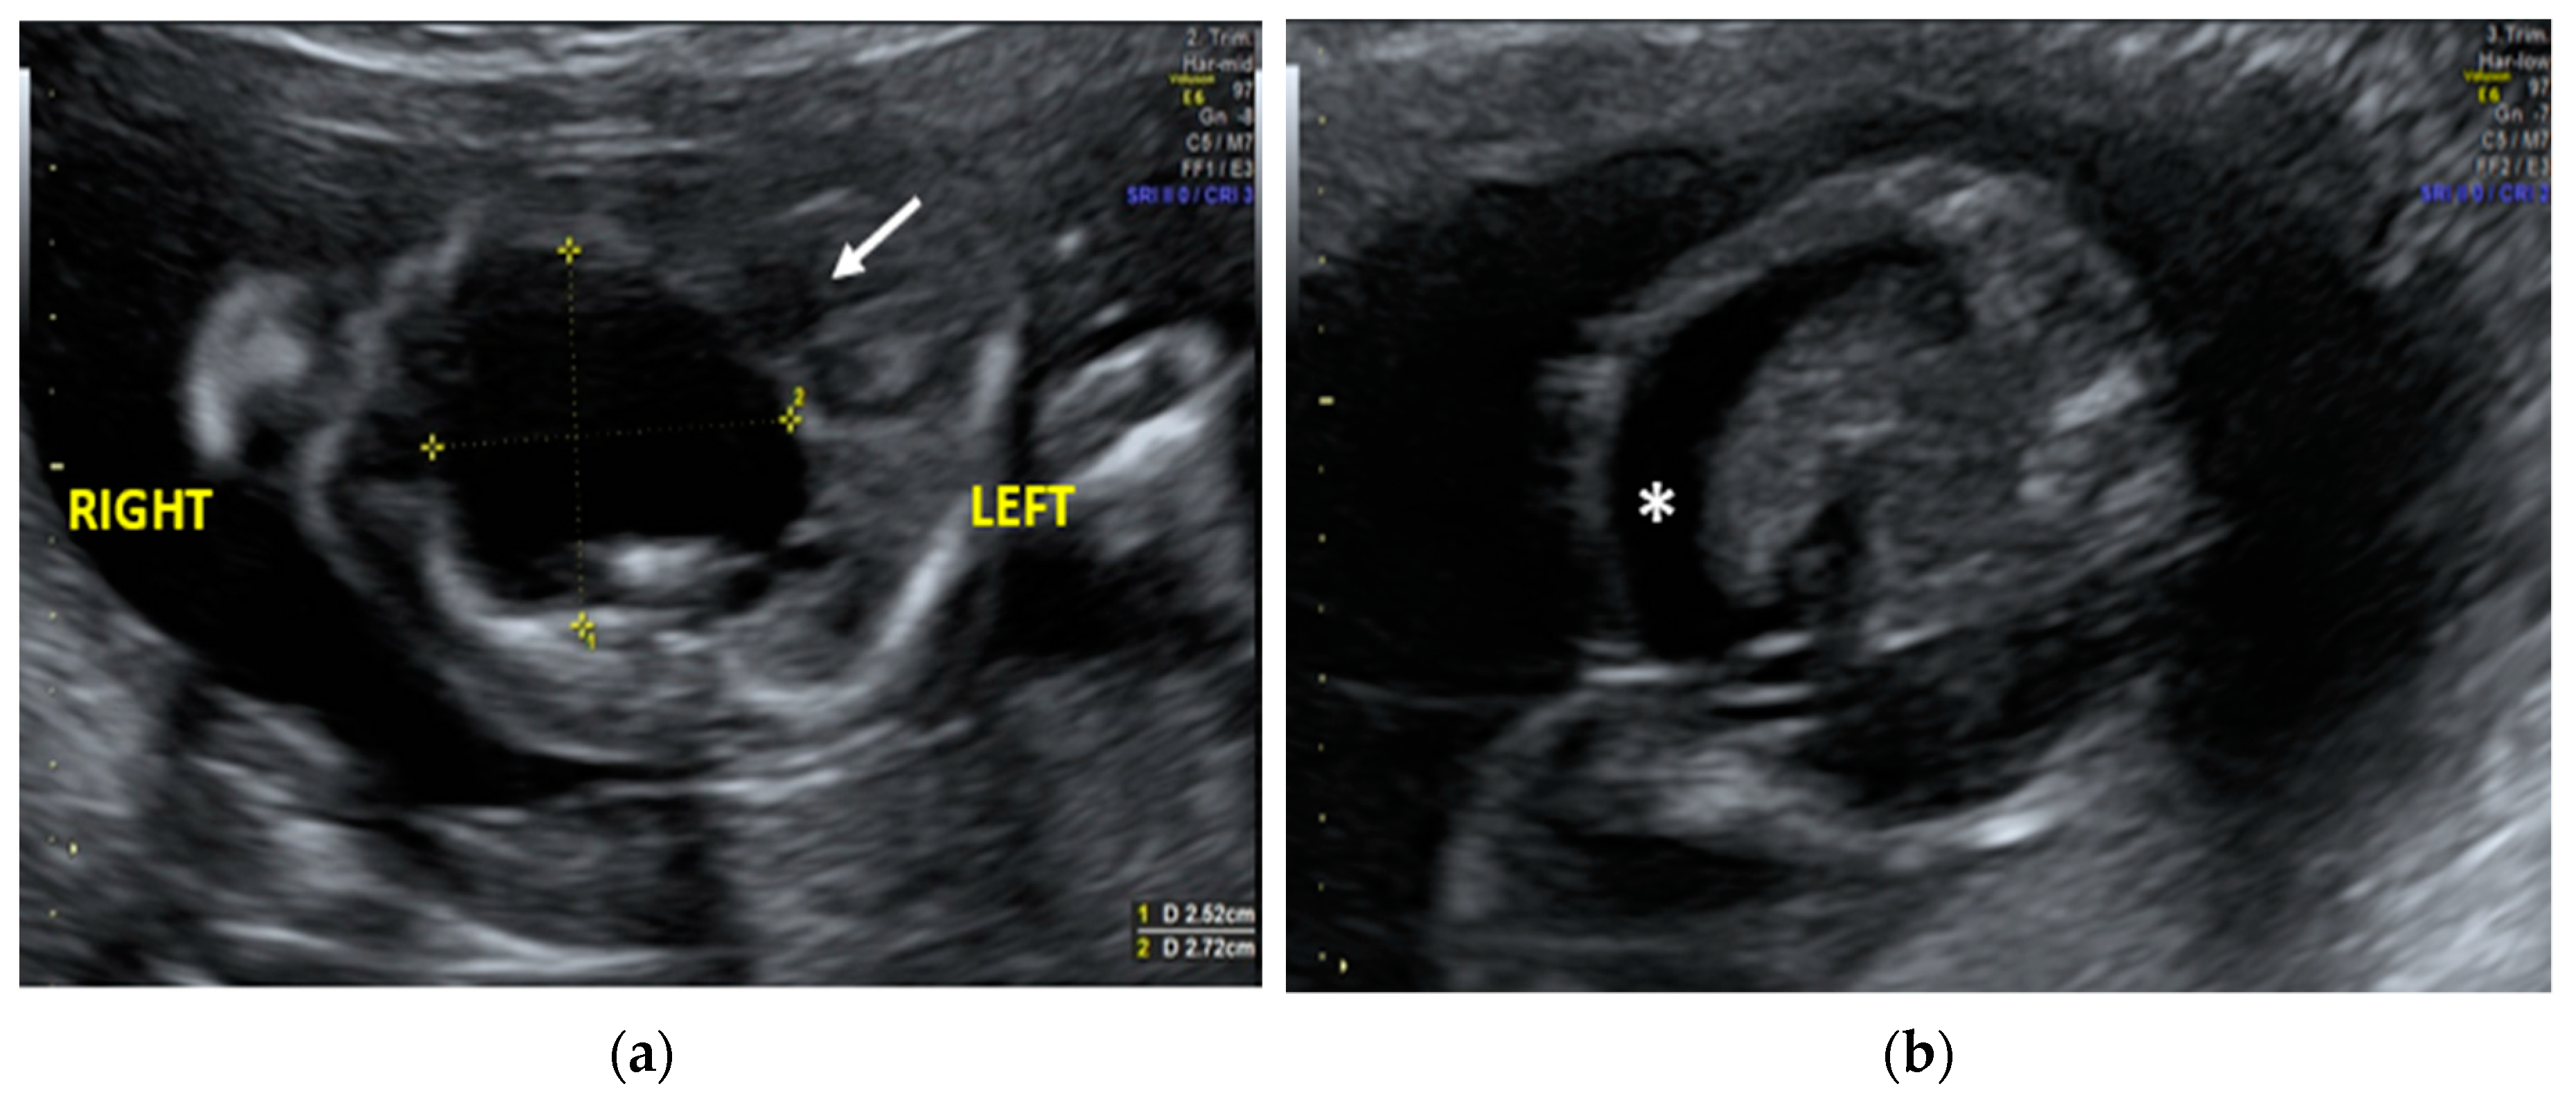

The morphological examination revealed the presence of a large anechoic cystic mass with unregular borders occupying the entire right hemithorax (LD = 2.7cm; APD = 2.5cm; TD = 2.4cm), which apparently originated from the lung parenchyma (Figure 1a). The cyst had no internal or perilesional vascularization. Fetal heart appeared to be anatomically normal, but it was extremely shifted on the left, together with the mediastinum, due to the compression caused by the cyst. The remaining fetal anatomy seemed to be regular, except for the presence of marked ascites (Figure 1b).

Figure 1. Transabdominal ultrasound managed at 23 weeks of gestational age according to amenorrhea (21.5 weeks according to first ultrasound): (a) Transverse fetal thoracic scan showing the large anechoic cystic formation occupying the entire right hemithorax. Fetal heart (arrow) and mediastinum were extremely shifted on the left due to the cyst compression; (b) Transverse fetal transabdominal scan showing marked ascites (*).